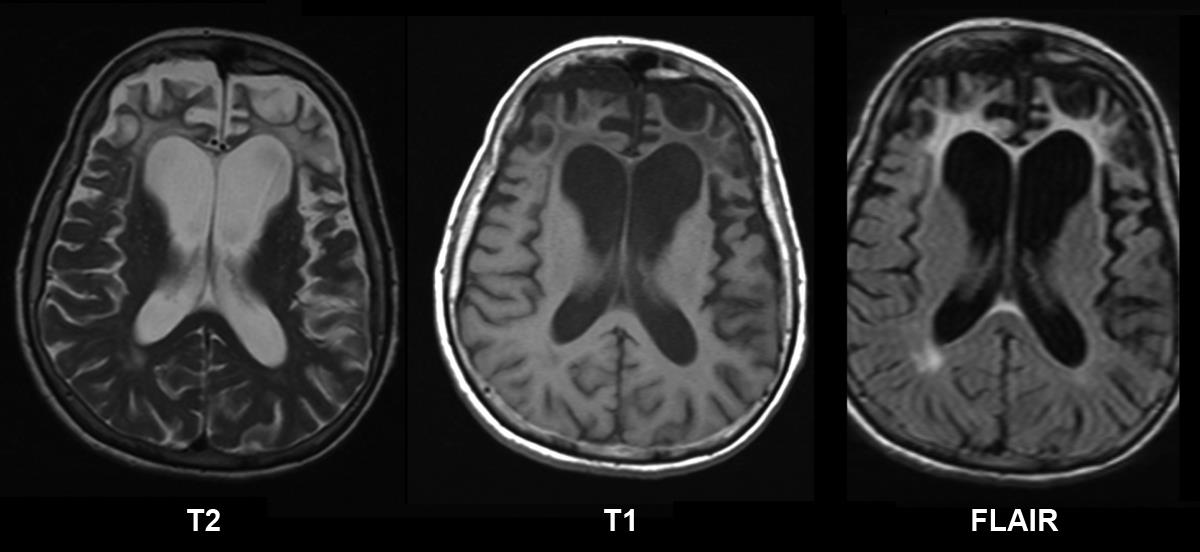

Pick's Disease Radiology . pick’s disease (pid) is a devastating neurodegenerative disease that is characterized by dementia,. the classic mr pattern of pick’s disease shows frontal and temporal cortical atrophy, prominent enlargement of. pick disease (named after arnold pick) is a progressive dementia defined by clinical and pathologic criteria. pick disease, also known as frontotemporal dementia, is the most common cause of dementia in patients. radiographically pick’s disease, a variant of frontotemporal dementia, appears as prominent atrophy of the temporal and/or. frontotemporal lobar degeneration (ftld) is the pathological description of a group of.

Pick's Disease Radiology the classic mr pattern of pick’s disease shows frontal and temporal cortical atrophy, prominent enlargement of. the classic mr pattern of pick’s disease shows frontal and temporal cortical atrophy, prominent enlargement of. pick disease (named after arnold pick) is a progressive dementia defined by clinical and pathologic criteria. frontotemporal lobar degeneration (ftld) is the pathological description of a group of. radiographically pick’s disease, a variant of frontotemporal dementia, appears as prominent atrophy of the temporal and/or. pick’s disease (pid) is a devastating neurodegenerative disease that is characterized by dementia,. pick disease, also known as frontotemporal dementia, is the most common cause of dementia in patients.